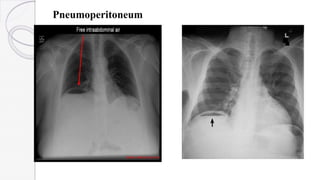

Pneumoperitoneum

“football” sign

 The median umbilical ligament and falciform ligament

are sometimes included in the description of this sign

Example of football sign: